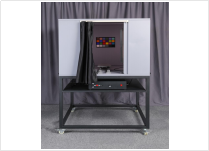

| 一體式測試平台 | 3nh內窺鏡測試平台 |

NK-1130-65 | 自帶暗室環境,能滿足目前NKTest軟件中所有包含的測試項要求 | |

| 一體式測試平台 | 3nh內窺鏡測試平台 |

NK-1130-65 | 自帶暗室環境,可以配合以上測試卡來進行測試 |